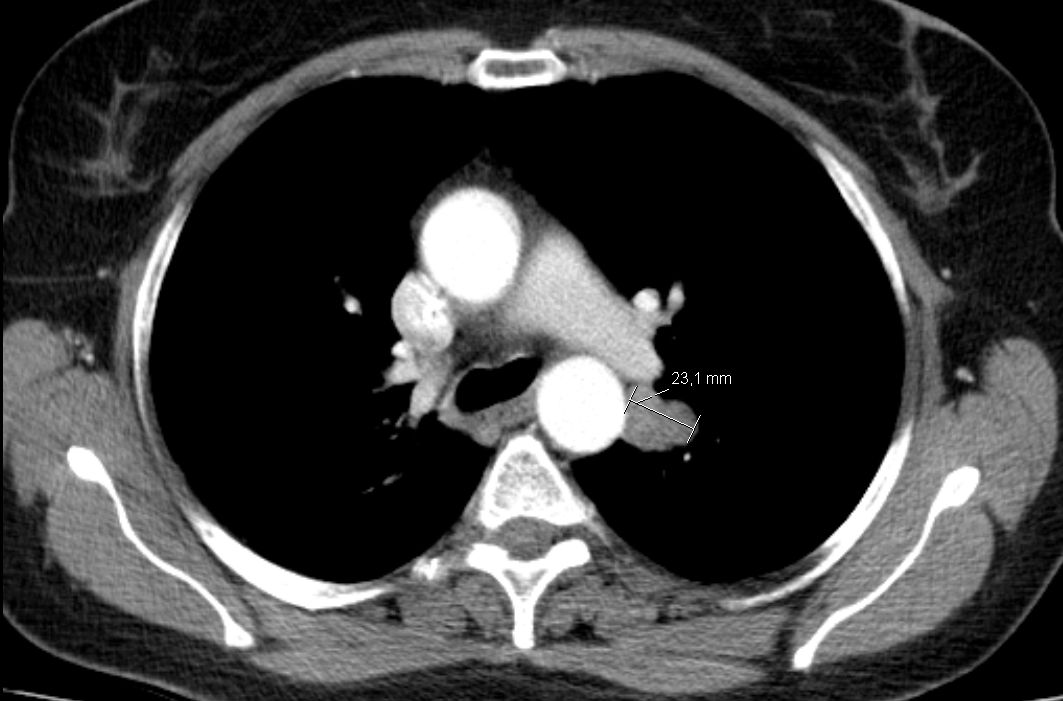

| Hirnmetastase | 48-jährige Frau, die vor 4 Jahren ein DLBCL Stadium IVa mit Bulk rechts inguinal, Lymphknoten mediastinal axillär links, Milzvergrößerung und pulmonale Infiltration hatte. 8mal R-CHOP, RT der rechts inguinalen Lymphknoten mit 26 Gy. Vor 5 Monaten Tumor linker Hilus und Hirnmetastase links occipito-parietal: Histologie: großzelliger neuroendokriner Tumor. Entfernung der Hirnmetastase, RT Neurocranium. 6 x Carboplatin/Etoposid: PR des Lungentumors, vitaler Resttumor des Gehirns | |||||||||||||||||||

CT: Tumor lateral der Aorta descendens![]() |